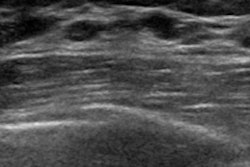

The CAD LUS4TB consortium, which includes 10 African and European research institutions, will be using a new AI algorithm in the initial trial that uses Butterfly’s software development platform. The platform automates image classification for TB from images obtained with Butterfly’s portable ultrasound devices, the Burlington, MA-based company said.

The initial trial for the project will open in September and will involve 3,000 adult patients across sub-Saharan Africa. The AI-enabled POCUS will be used to help nonradiologist frontline healthcare workers to more quickly and accurately identify TB in patients.